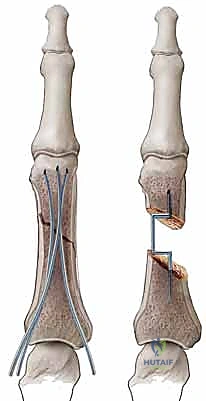

* FIG 1 • A. Unstable PIP fracture-dislocation. The upward pull of the central tendon insertion and the distal superficialis insertion pull and push the middle phalanx up and over the proximal phalangeal head. The only forces preventing dorsal subluxation are the middle phalanx palmar lip and the palmar plate, both of which are lost in an unstable PIP palmar lip fracture.

*

* FIG 1 • B. PIP instability after a fracture. A direct relation exists between the amount of middle phalanx palmar lip destroyed by the fracture and the resultant PIP joint stability. Articular damage in excess of 50% of the joint surface always renders the joint unstable, whereas fractures involving less than 30% usually are stable. Tenuous fractures (ie, those with articular damage of 30% to 50% of the joint surface), must be assessed with lateral radiographs. If the joint will not stay reduced with less than 30 degrees of flexion, it must be classified as “unstable.”